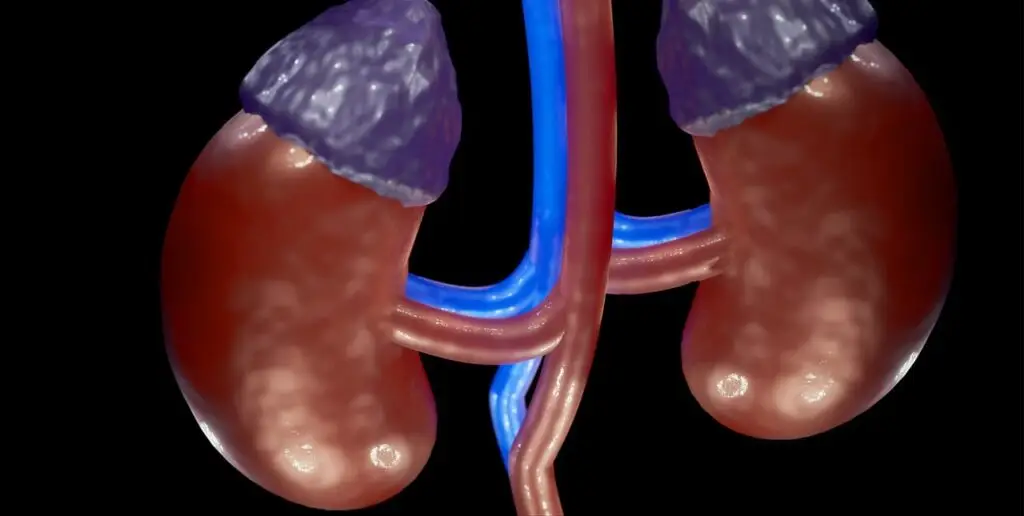

Adrenal Issues

We also treat adrenal issues such as adrenal tumors, adrenal insufficiency